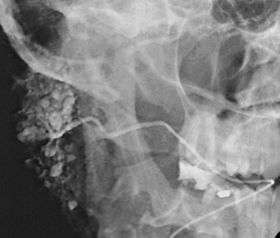

Sialogram in a patient suspected of Sjögren's syndrome | |

Sialography (also termed radiosialography) is the radiographic examination of the salivary glands. It usually involves the injection of a small amount of contrast medium into the salivary duct of a single gland, followed by routine X-ray projections.[1]

The resulting diagram is called a sialogram.

This study is interpreted by evaluating the morphology of the salivary ducts for obstructions and chronic inflammation. Sialodochitis is a term describing dilation of the ducts caused by repeated inflammatory or infective processes. There is also irregular salivary duct stricture (narrowing) of the duct, which creates an appearance known as "sausage link" pattern on a sialogram. Suggestions of abscesses and autoimmune diseases such as Sjögren syndrome can also be elicited. Sialadenitis is inflammation of the salivary glands, which may cause acinar atrophy and create an appearance known as "pruning of the tree" on a sialogram, where there are less branches visible from the duct system. A space occupying lesion that occurs within or adjacent to a salivary gland can displace the normal anatomy of the gland. This may create an appearance known as "ball in hand" on an sialogram, where the ducts are curved around the mass of the lesion.[3]